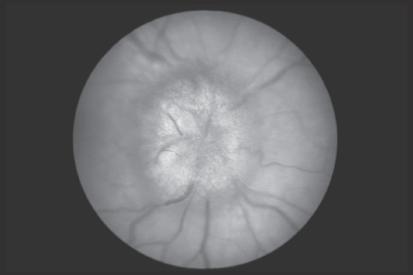

Direkte Spiegelung des Augenhintergrunds:

• Normale Papille: Scharfe Begrenzung, rötlich gelbe Farbe (vital).

• STP (▶ Abb. 1.2): Unscharf begrenzt, erhaben, später radiäre Blutungen.

• Optikusatrophie: Temporales Abblassen der Papille.

• Optikusneuritis: Normale Papille!

• Hypertensive o. diabet. Retinopathie: Lumeneinengung der Netzhautgefäße, Hämorrhagie, diffuses Netzhautödem.

Abb. 1.2 Stauungspapille [M139]